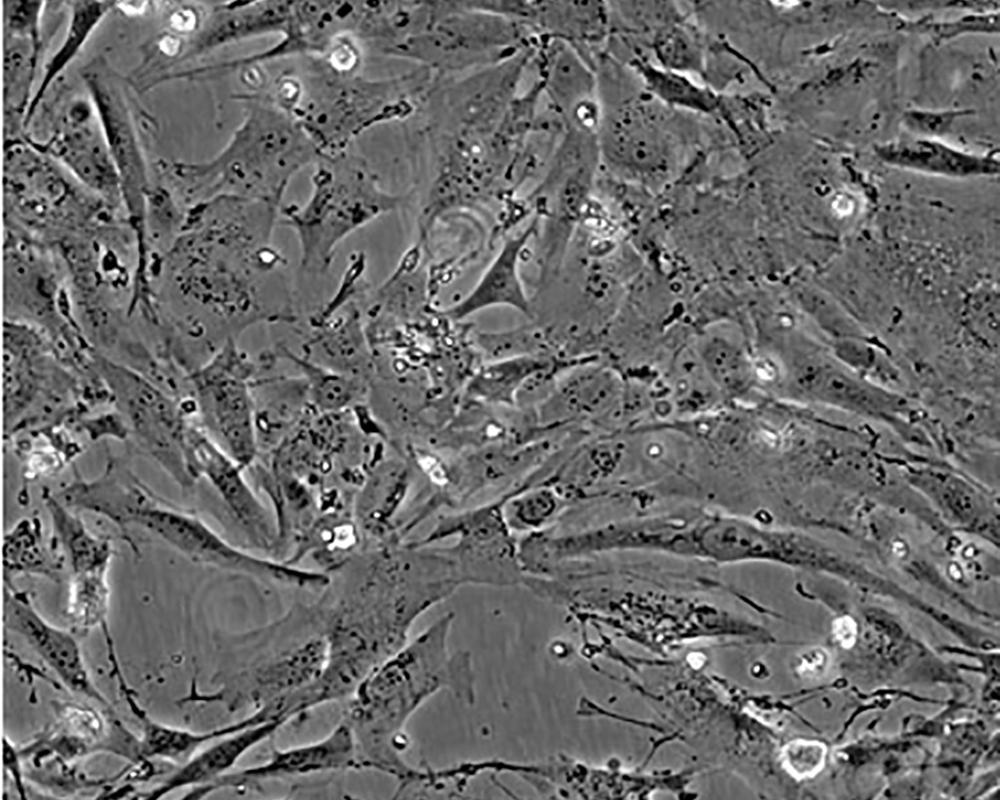

形態(tài)特征 epithelial

細胞描述 The Hs 578T line had a mixed polygonal morphology initially, but a stellate cell type was selected for during passage and by cloning. Aggregates of casein protein granules, desmosomes, tight junctions, lipid droplets and vesicularized smooth endoplasmic reticulum were observed by electron microscopy. As with Hs 578Bst, no estrogen receptors or endogenous viruses were detected.